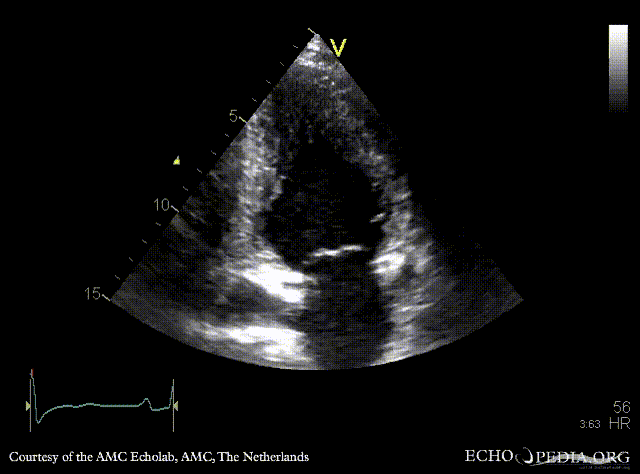

Case 42